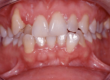

Per i pazienti in età infantile, caratterizzati dalla presenza di dentatura decidua, si procede con tutta una serie di interventi terapeutici intercettivi e preventivi. Attraverso l’utilizzo di apparecchi amovibili si cerca di guidare la crescita e lo sviluppo della futura dentatura, veicolando i denti verso la direzione corretta per l’occlusione.

Nei pazienti in età adulta, provvisti dunque di dentatura definitiva, si procede con apparecchiature solitamente fisse, che influenzano il movimento dentale agendo particolari e calibrate pressioni costanti, allo scopo di armonizzare ed equilibrare il rapporto tra l’arcata superiore e l’arcata inferiore.